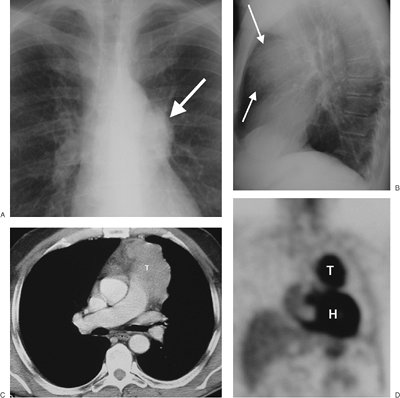

FIGURE 6-14. Thymic carcinoma. A: PA chest radiograph shows an abnormal left mediastinal contour (arrow). B: Lateral view shows abnormal opacity in the retrosternal area (arrows). C: CT scan shows a lobulated mass of homogeneous soft tissue attenuation (T) in the anterior mediastinum. D: Coronal positron emission tomographic scan shows normal activity in the heart (H) and abnormal activity in the thymic mass (T).